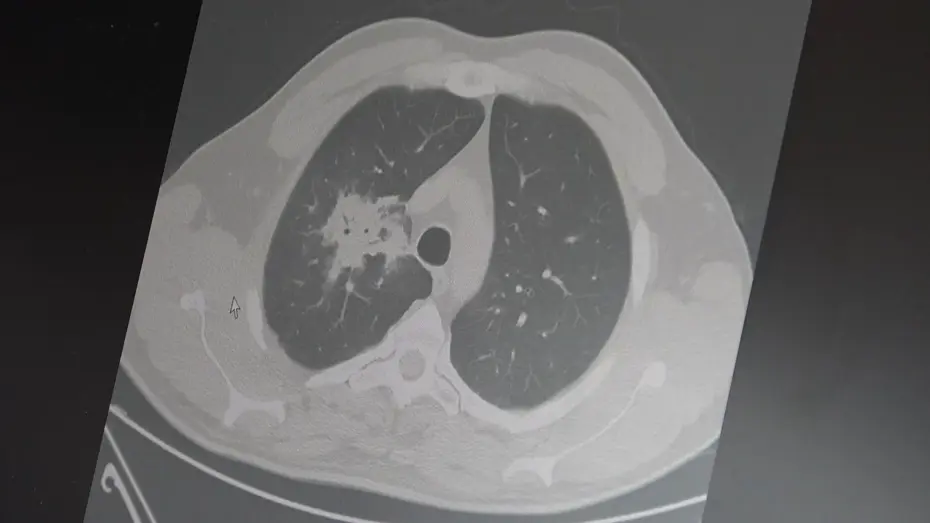

Özkaya, 100'den fazla bilimsel çalışmanın incelendiğini belirterek elektronik sigaraların özellikle akciğer ve ağız bölgelerinde kanser riskini artırabileceğine dair güçlü bulgular bulunduğunu belirtti.

Araştırmalarda insan, hayvan ve laboratuvar verilerinin birlikte değerlendirildiğini aktaran Özkaya, elektronik sigaraların içerdiği kimyasalların hücre düzeyinde zarara yol açtığının ortaya konulduğunu vurguladı.

Elektronik sigaraların DNA hasarı, oksidatif stres ve kronik iltihaplanma gibi kanser gelişiminde kritik rol oynayan üç temel mekanizmayı tetiklediğini belirten Özkaya, "Bu üç faktörün doğrudan kanser oluşumuna neden olduğunu biliyoruz" şeklinde konuştu.

2024 yılında yayımlanan bir çalışmaya da değinen Özkaya, hem geleneksel sigara hem de elektronik sigara kullanan bireylerde akciğer kanseri riskinin, sadece sigara içenlere göre dört kat daha fazla olduğunun bildirildiğini kaydetti.